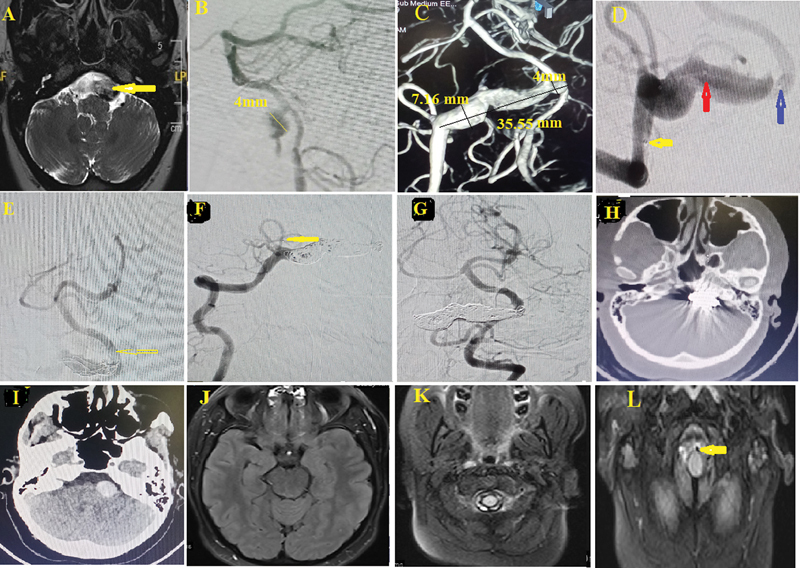

椎动脉巨大梭状动脉瘤并不常见,通常与旋转血流引起的血栓形成有关,表现为髓质区肿块效应,神经体征和症状进展缓慢。已经描述了搭桥手术、血管内手术和近端闭塞和分流器放置联合诱捕和结扎;然而,最佳治疗方法仍有争议。一名35岁女性向我们就诊,主诉为轻度枕部头痛,右侧颈背区域中度疼痛,麻木和刺痛感转移至右上肩1个月。颈椎及脑部核磁共振显示颈椎正常。脑MRI和数字减影血管造影显示椎动脉V4段几乎完全血栓形成的巨大梭状动脉瘤。患者接受血管内完全线圈充填治疗。术后情况顺利。她在手术的第7天出院。血管内线圈栓塞治疗血栓形成的巨大梭状V4段椎动脉动脉瘤是安全有效的。

Giant fusiform aneurysm of the vertebral artery is not common and is usually associated with thrombosis due to swirling blood flow, and manifests as mass effect on the medullary region with slow progression of neurological sign and symptoms. Trapping and ligation combined with bypass surgery, endovascular surgery, and proximal occlusion and flow diverter placement have been described; however, the optimal treatment is still debatable. A 35-year-old female presented to us with complaints of mild occipital headache, moderate pain over the right side of the nape region, numbness, and tingling sensation transferring to the right upper shoulder for 1 month. Magnetic resonance imaging (MRI) of cervical spine and brain revealed normal cervical spine. Brain MRI and digital subtraction angiography were done that revealed an almost completely thrombosed giant fusiform aneurysm of the V4 segment of the vertebral artery. Patient underwent endovascular therapy with complete coils packing. Postoperative status went uneventful. She was discharged on the 7th day of procedure. Complete occlusion of thrombosed giant fusiform V4 segment vertebral artery aneurysm by endovascular therapy with coils embolization is safe and effective.